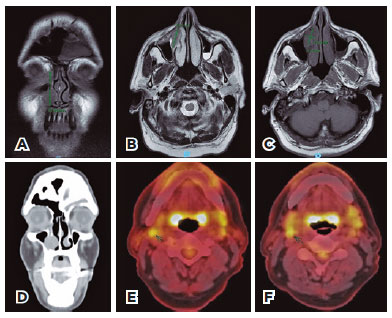

Further, magnetic resonance imaging (MRI) revealed a 4.2 x 2.6 x 1.5-cm ill-defined mass occupying the lacrimal sac fossa and the nasolacrimal duct, located between the medial wall of the maxillary sinus and the inferior nasal concha (Figure 2A-2C); same findings were observed in the tomographic images obtained using positron emission tomography with computed tomography (CT) scan positron emission tomography (PET-CT) (Figure 2D). The lesion showed isosignal on T1-weighted images, slight hypersignal on T2-weighted images, and intense contrast uptake. PET-CT demonstrated involvement of two lymph nodes in the upper right jugular chain (Figures 2E-2F).

14-fig02.jpg)